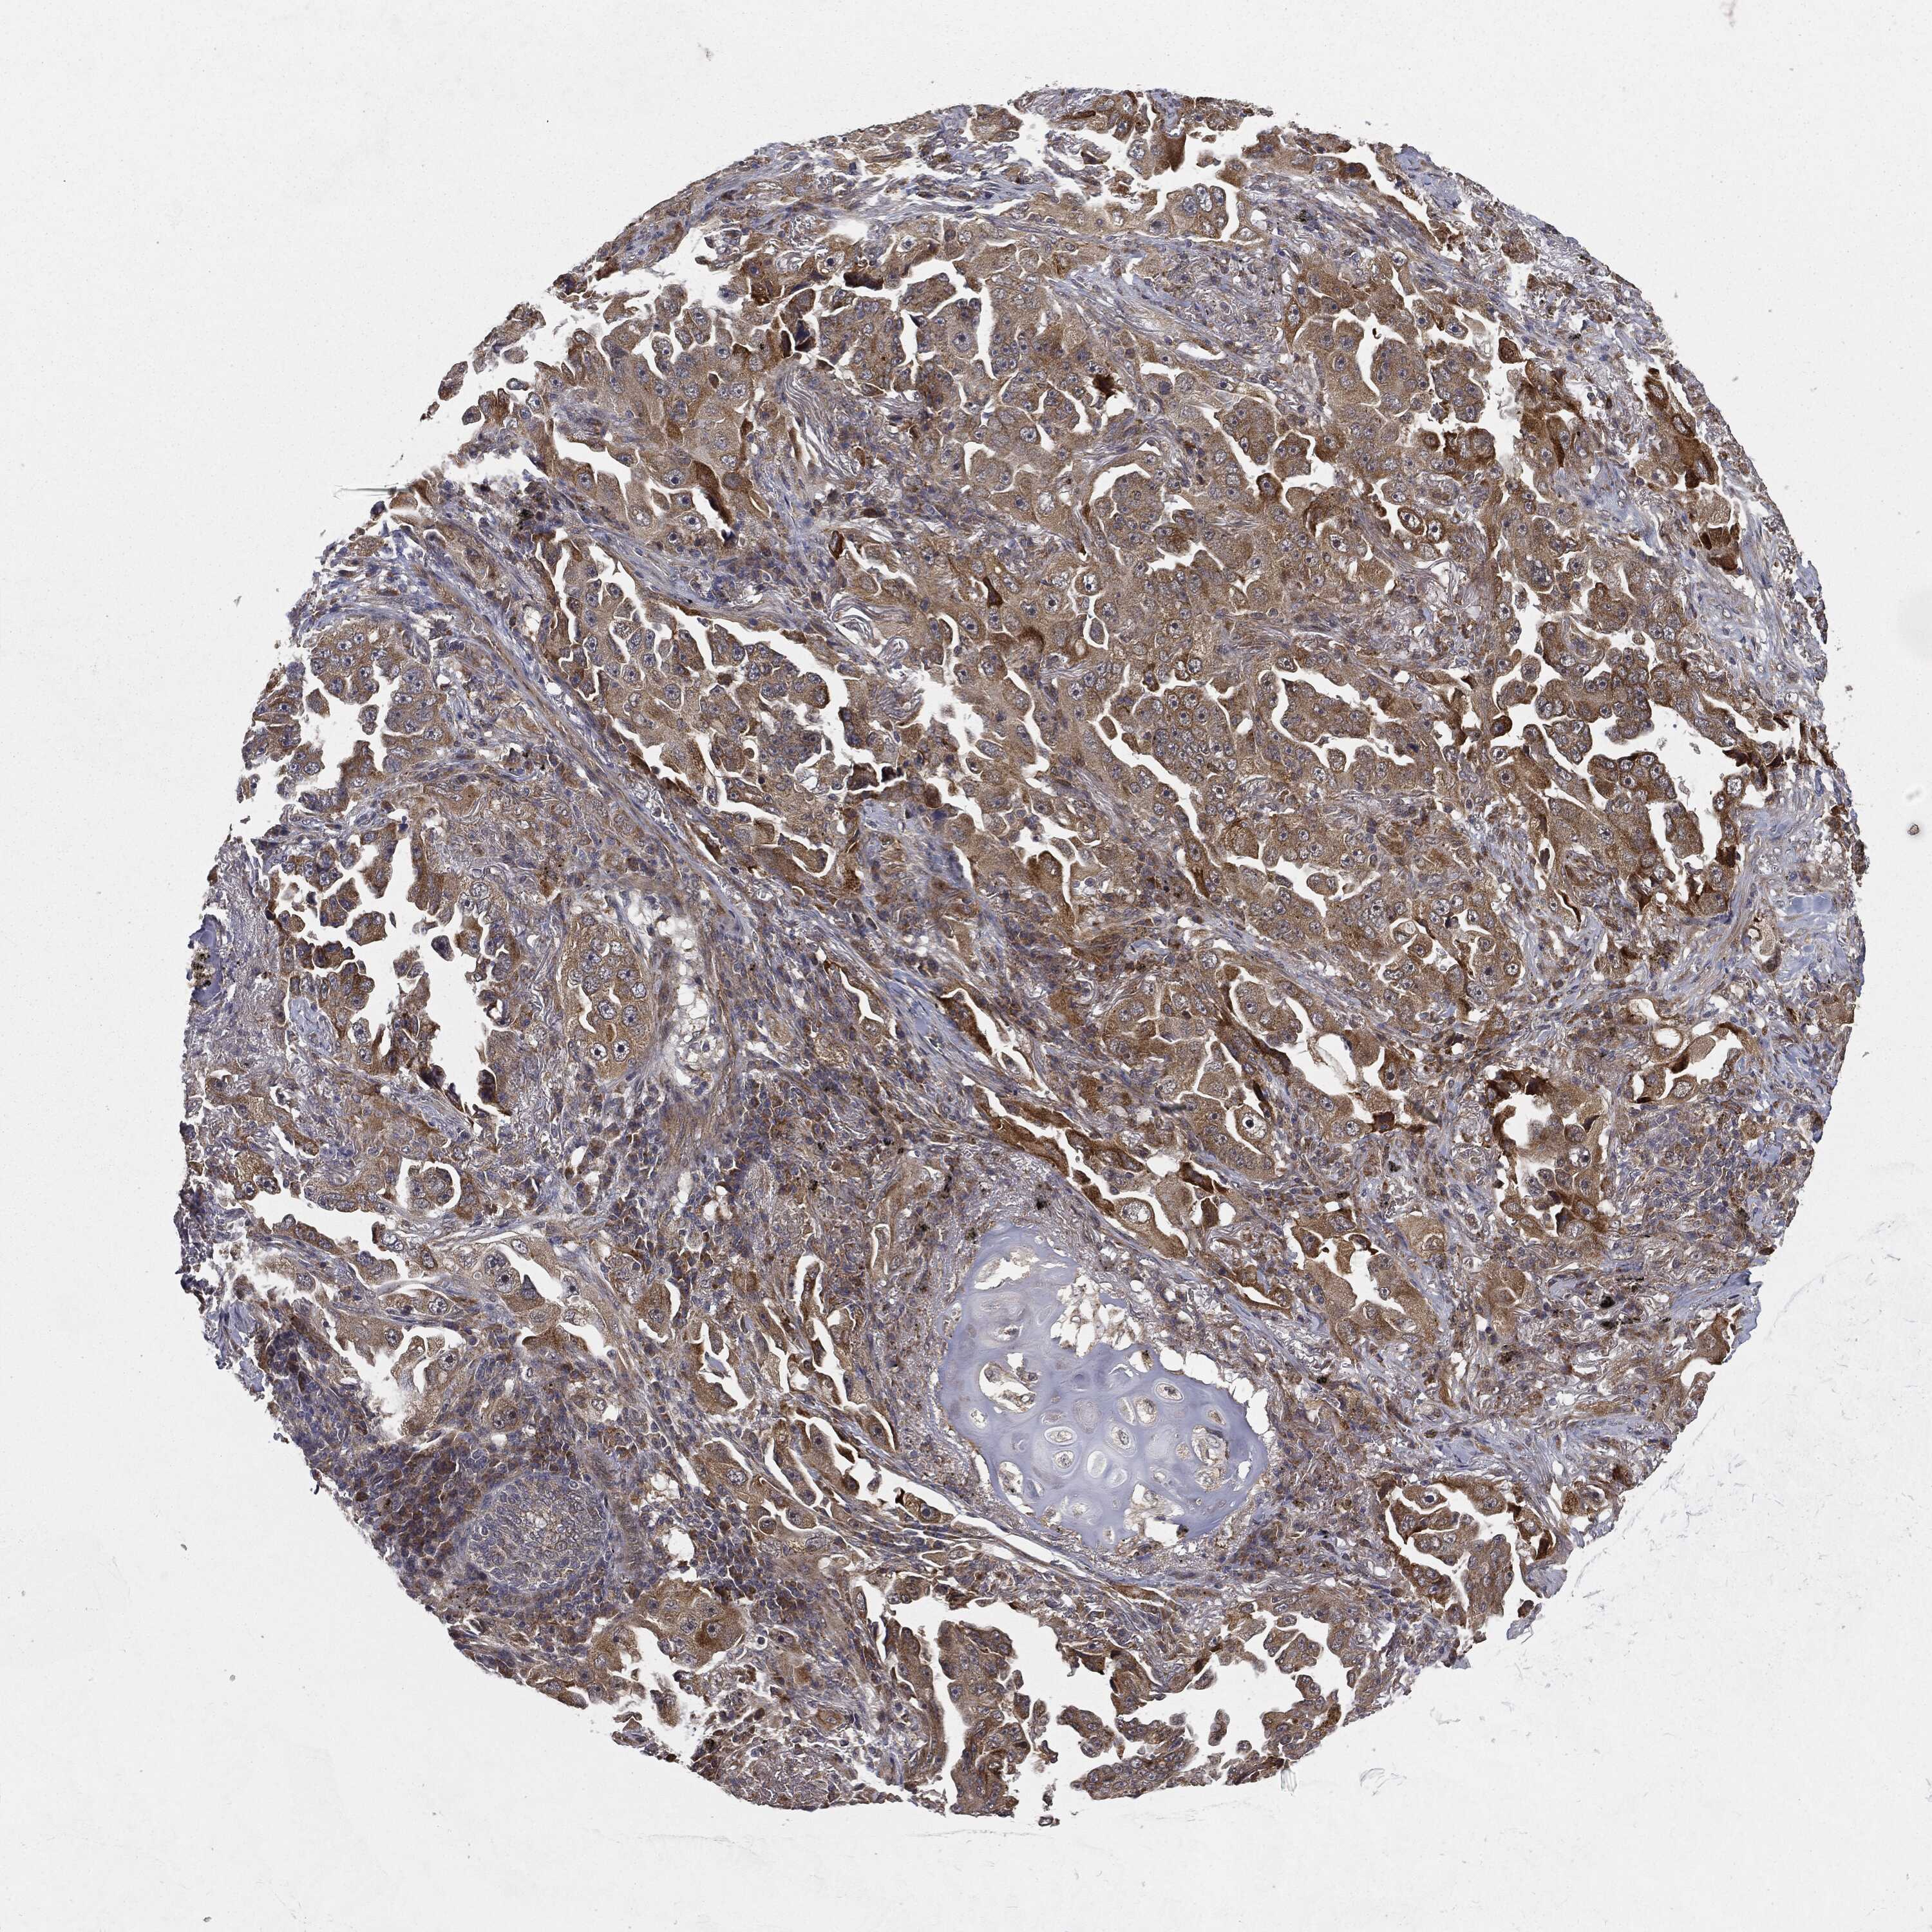

CANCER LUNG CANCER Show tissue menu

LUAD TCGA LUAD VALIDATION LUSC TCGA LUSC VALIDATION PROTEIN LUAD CPTAC PROTEIN LUSC CPTAC PROTEIN EXPRESSION

ANTIBODIES

AND

VALIDATION